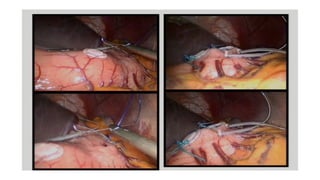

Management of

Gastroparesis

Surgical treatment options